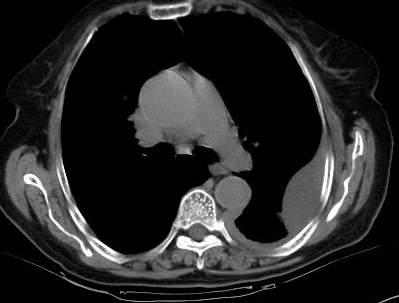

标题: CT0563:病历讨论,胸膜间皮瘤? [打印本页]

标题: CT0563:病历讨论,胸膜间皮瘤?

测ct值3-6hu,

既然ct值是3-6hu,还不如考虑包裹性积液。

支持包裹性胸腔积液。

请上传纵隔窗。目前还是支技包裹性积液(明显梭形),即使是间皮瘤并积液也少梭形的。

从图片看,包裹性积液好象更合理,梭形,ct值3-5hu(在哪看到的?);胸膜间皮瘤如此规则,不多见。

左侧背部胸膜肥厚,伴包裹性积液,不考虑间皮瘤.

同意以上各位的高见,首先考虑包裹性积液,1.胸膜间皮瘤积液量一般较大,以游离性积液更为常见,2.可以看到增厚的胸膜结节